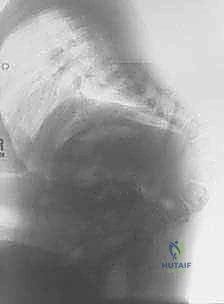

- التصوير الطبي المتقدم: يطلب الدكتور هطيف صور أشعة سينية بانورامية، أشعة مقطعية ثلاثية الأبعاد (3D CT Scan) لفهم التشريح العظمي المشوه، ورنين مغناطيسي (MRI) لتقييم الحبل الشوكي والتأكد من عدم وجود "الحبل الشوكي المربوط" (Tethered Cord).

المرحلة الثانية: الإجراء الجراحي خطوة بخطوة

- التخدير وتجهيز المريض: يتم تخدير الطفل بعناية فائقة، ووضعه على طاولة العمليات بوضعية تحمي الأعضاء الداخلية.

- الشق الجراحي والتعامل مع الأنسجة: يتم فتح الجلد بحذر شديد. في كثير من الأحيان، يتم استئصال الأنسجة الندبية القديمة. يستخدم الدكتور هطيف تقنيات الجراحة المجهرية (Microsurgery) للتعامل مع الأنسجة العصبية الرقيقة وتجنب تسرب السائل النخاعي.

- استئصال الفقرات (The Kyphectomy): هذه هي الخطوة الأكثر حساسية. يقوم الدكتور هطيف بتحديد الفقرات التي تشكل قمة الانحناء (عادة من 1 إلى 3 فقرات). يتم استئصال جسم هذه الفقرات بالكامل مع الأقراص الغضروفية المحيطة بها.

- تصحيح التشوه (Closing the Wedge): بعد إزالة الفقرات، يصبح العمود الفقري مرناً في تلك النقطة. بمهارة فائقة، يقوم الدكتور هطيف بضم الجزأين العلوي والسفلي من العمود الفقري معًا، مما يلغي الانحناء ويستعيد استقامة الظهر.

- التثبيت الميكانيكي (Spinal Fixation): للحفاظ على هذا التصحيح، تُستخدم براغي وأعمدة معدنية مخصصة للأطفال. يتأكد الدكتور هطيف من تثبيت هذه الأدوات بقوة في الحوض والفقرات السليمة لضمان ديمومة النتيجة.

- الترقيع العظمي (Bone Grafting): يتم وضع طعوم عظمية (غالباً من العظام التي تم استئصالها) حول منطقة الجراحة لتحفيز التحام العمود الفقري بيولوجياً لتكوين كتلة عظمية صلبة واحدة.